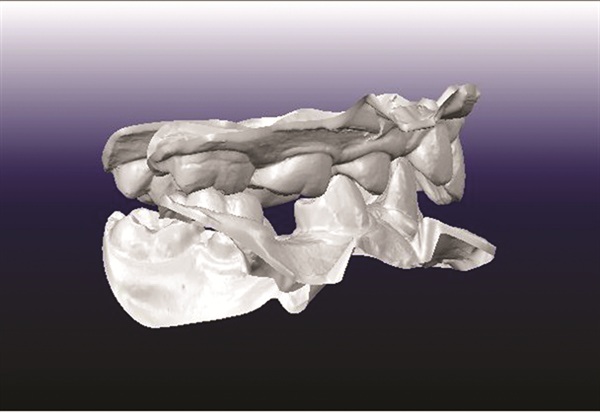

A 12-year-old male presented with severe Class II, deep bite, and significant crowding. The original poster was torn between two conflicting clinical pictures. Half the diagnostic findings pointed toward extraction: second molars impacted in the ramus, a blocked lower left canine, blocked maxillary canines, and a nearly full-step Class II relationship. The other half suggested non-extraction with vertical control to avoid deepening the bite further. The concern was that by the time crowding was resolved and the deep bite corrected, the incisors would be too flared for effective Class II correction without further proclination. The question posed to the forum was whether immediate upper first premolar and lower second premolar extractions were the best route forward (Figs. 1–11).

Fig. 1